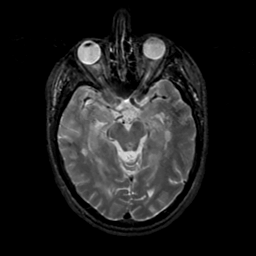

MR Study #17, July 7, 1991 -- Slice #20